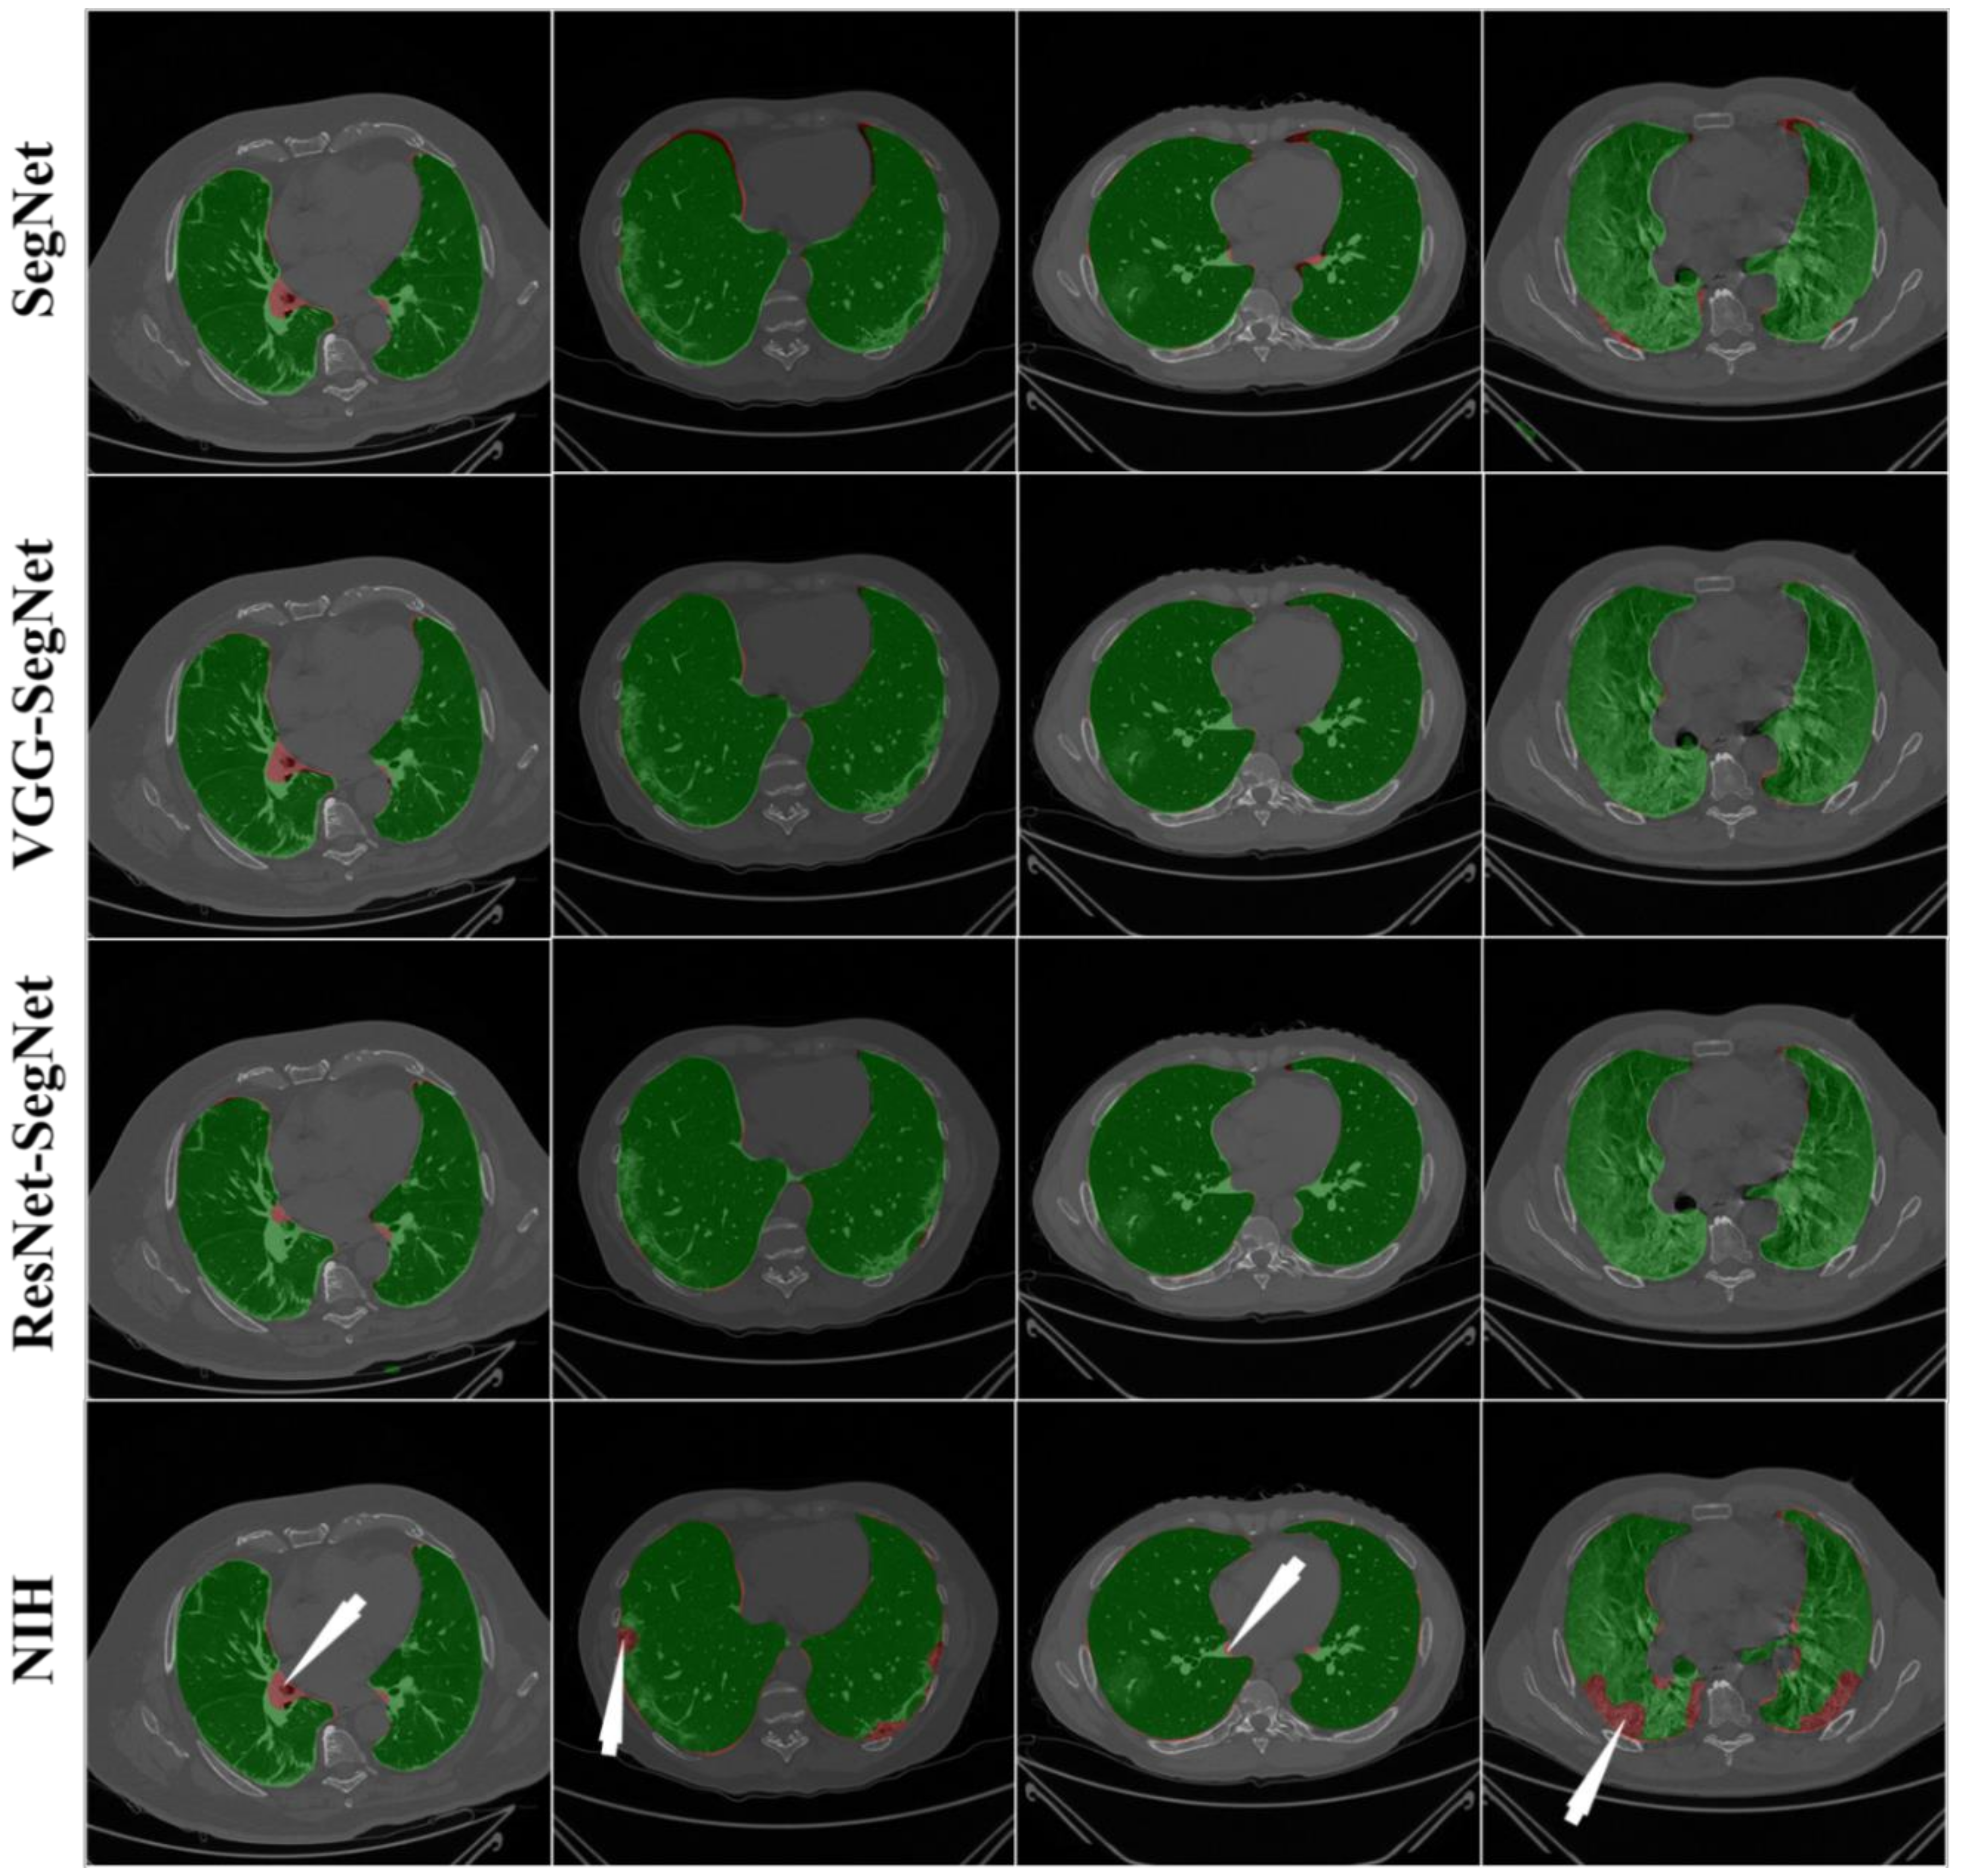

4.2.1. Visualization of Lung Boundary and Regional Lung Error